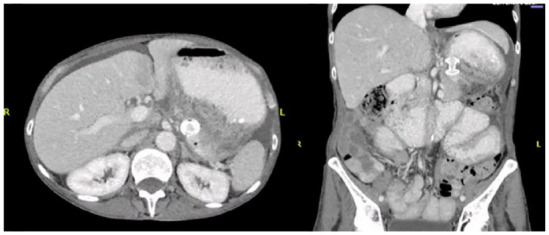

Endoscopic ultrasound-guided drainage of loculated malignancy-related ascites has been reported in limited case series with success in achieving symptomatic relief. In this case report, we detail the successful drainage of a loculated paragastric ascites with insertion of a lumen-apposing metal stent (LAMS) in a patient diagnosed with metastatic ovarian cancer.

Abstract Image